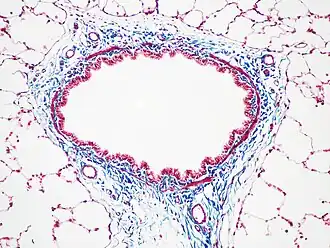

Бронх крысы, окраска трихромом Массона -